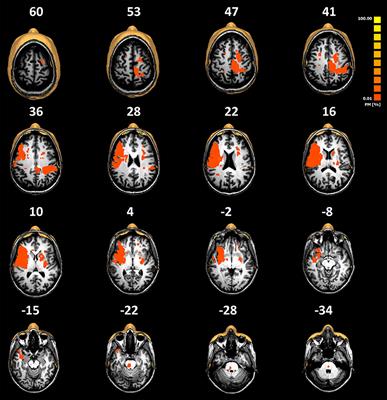

Original Research

Published on 15 Oct 2021

in Movement Disorders